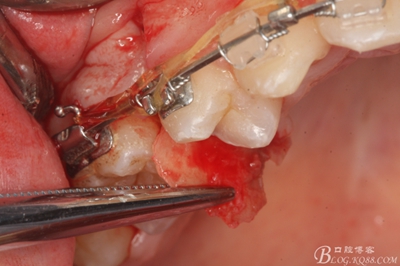

圖13. 用小球鉆去除約1mm牙槽骨,暴露15牙根面約5mm。

圖14.用小球鉆縱分15牙根